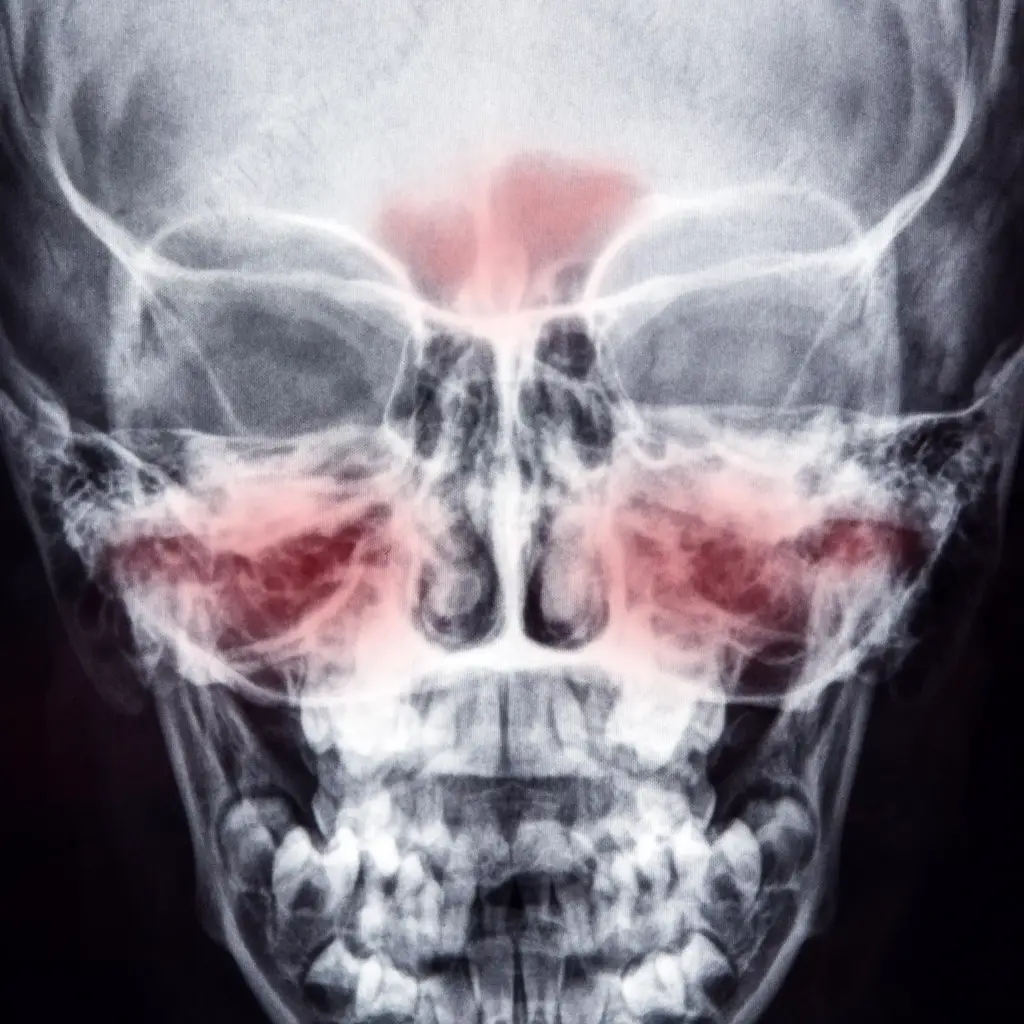

牛津大学出版社出版的《风湿病学实践进展》(Rheumatology Advances in Practice)中的一篇新论文指出,多发性肉芽肿病(Granulomatosis With Polyangiitis)是一种导致血管发炎的鼻部疾病,通常在鼻窦、喉咙、肺部和肾脏出现症状,可能经常被误诊。研究人员认为,许多被确认为鼻窦和鼻腔局限性疾病的患者实际上可能是由于使用可卡因而导致的鼻腔损伤。

可卡因是英国第二大最常滥用的药物,16至59岁的人口中有2.6%使用可卡因。美国约有480万人(或12岁以上人口的1.7%)报告在过去一年使用过可卡因。可卡因可引起重大健康问题,包括可卡因引起的中线破坏性病变和各种其他血管问题。然而,有证据表明,使用可卡因可引发某些抗体的产生,从而导致临床表现与特发性肉芽肿病(GPA-以前称为韦格纳肉芽肿病)非常相似。

加上偶尔出现的一般症状,如关节痛、疲劳和皮疹,GPA与可卡因所致损害之间的相似性使医生难以诊断。虽然GPA很罕见,每10万人中大约有3人受到影响,但研究人员认为,误诊的可能性很严重,因为GPA的常见治疗方法对正在使用可卡因的人来说可能是无效的,甚至是危险的。